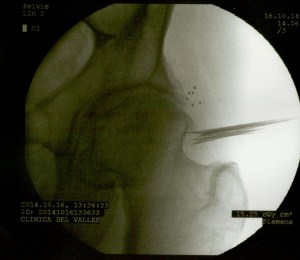

A continuación las imágenes de radioscopía que corresponden al paciente en cuestión. Se observan en primer lugar la colocación de las agujas que vehiculizan los microimplantes, y éstos (pequeños puntos) ubicados próximos a la ceja cotiloidea y a la osteofitosis de la cabeza del fémur.